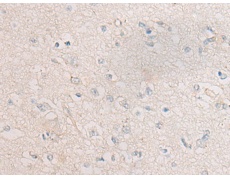

IHC positive control: |

Human liver cancer and Human gastric cancer |